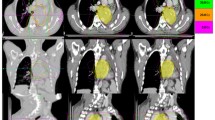

A tumour dose of 45 Gy in 5 fractions was prescribed to the PTV in all the plans. The plan characteristics in various planning systems were listed in Table 2 below. The Cyberknife plans were created using an IRIS beam collimation system, whereas the HT plans used an MLC leaf width of 0.625 cm projected to the isocenter. The VMAT plans were generated with APEX MLC with a 2.5 mm resolution at the isocenter. For Cyberknife plans, the minimum collimator size was maintained above 10 mm. HT planes with a dynamic jaw size of 2.51 cm field width with a pitch of 0.2 and a modulation factor of 2.0 were developed in helical delivery mode. The optimization algorithms used by the Cyberknife, HT, and VMAT treatment planning systems differ. Within each treatment planning system, however, the planning constraints were set the same to obtain the largest target coverage.The overlaid PTV contours for UL, ML, and LL tumour are shown on DIBH images in Fig. 1.

CT images showing the overlay of PTV derived from ITV in: transverse images for tumours in a UL, b ML, c LL for left, right and left lung tumours: coronal plan images d UL, e ML, f LL and sagittal plan images g UL, h ML, i LL. The PTV contours drawn on their respective image sets overlaid on DIBH images in red, yellow, green, blue and orange colors for 0-view, 1-view, 2-view, AveIP and DIBH techniques respectively